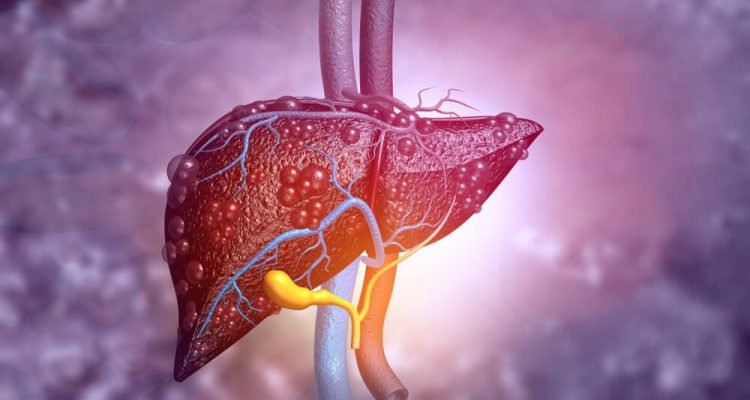

Kepenys yra atsakingos už angliavandenių skaidymą, gliukozės gamybą ir organizmo detoksikaciją. Jos taip pat kaupia gyvybiškai svarbias medžiagas ir gamina aliejų, kuris būtinas tinkamam maisto produktų virškinimui ir gyvybiškai svarbių medžiagų įsisavinimui.

Kepenų funkcijos sutrikimai gali sukelti kepenų ligas, sutrikusią medžiagų apykaitą ir net 2 tipo diabetą. Yra keletas maisto produktų ir gėrimų, kuriuos vartojant galima apsaugoti kepenis.